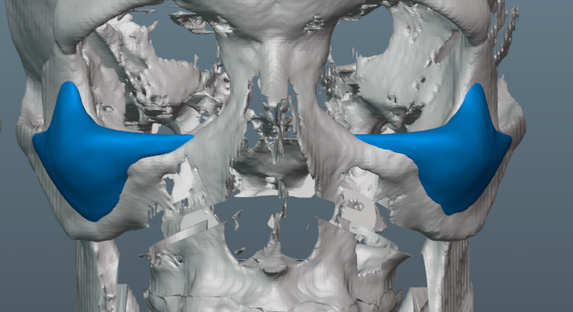

Putting all malar implants in the same category kills all nuance. A lot of malar implants place volume on the lower sections of the zygoma which adds vertical height to the cheekbones which does not look very good. In addition, if you don't have dimorphism in other parts of your face they will looks strange/gay and will throw off harmony. They have to be done right.Malar implants give a very feminine look to the face. On a man it will look very ‘gay-like’. Apple cheek look. Ideal for women maybe but absolutely not for men.

These are normie implants, you see they are tall and reach the bottom of the zygoma

View attachment 4827391

These type of implants are better as they are higher set and don't increase lower zygomatic protrusion (which is what you want)

These are normie implants, you see they are tall and reach the bottom of the zygoma

View attachment 4827391

These type of implants are better as they are higher set and don't increase lower zygomatic protrusion (which is what you want)